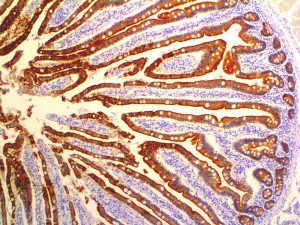

This activation induces inflammatory monocytes to highly express IL-6, starting a localized and then systemic cascade effect that results in hyperproduction of IL-6, which accelerates the inflammatory process. Because IL-6 also increases vascular permeability, excessive levels cause blood vessels to become very leaky. This, along with clotting factors released from vascular endothelial cells, stimulates the coagulation cascade, resulting in microthrombosis (tiny clots), which leads to ischemia and tissue death of the kidney, intestines, heart, liver, brain and extremities.